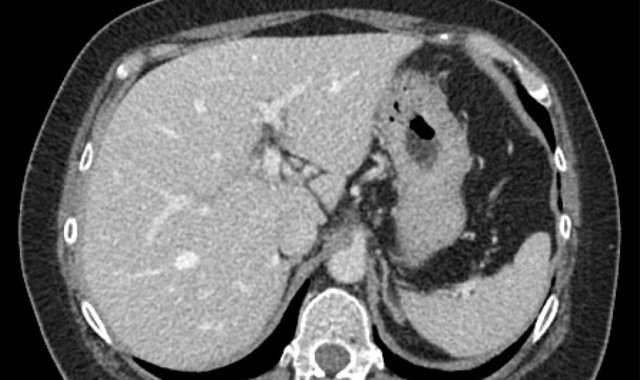

The images show an only mild rim-like arterially enhancing lesion in segment V with washout.

A linear area of hypoenhancement is seen extending from the mass which is suspicious of tumor in vein (yellow arrow).

Since we are not absolutely sure that it is a tumor thrombus, we cannot categorize this as LR-TIV.

A follow up CT was done, showing severe progression of the tumor as well as vascular involvement of the anterior right portal vein (white arrow).

Now we are sure of tumor invasion in the portal vein.